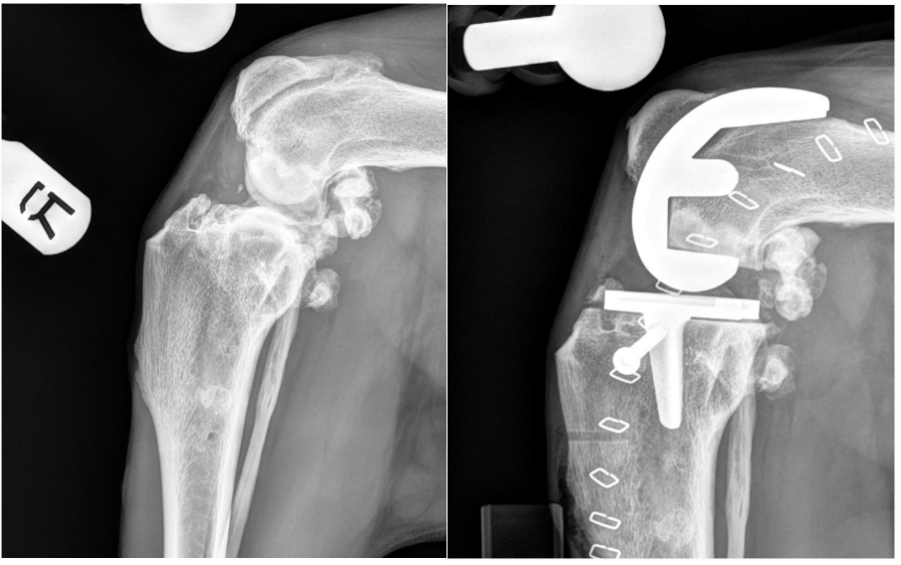

Elbow OA often arises from elbow dysplasia, such as medial coronoid disease or trauma. Progressive cartilage loss produces painful crepitus, swelling, restricted range of motion, and lameness that typically waxes and wanes but trends worse over time, limiting daily function and activity.

Modern total elbow replacement (TER) uses cementless, porous implants. Current designs couple a humeral component to a radial/ulnar construct with the radius and ulna fused; substantial pain relief is expected, though a residual gait asymmetry is typical due to altered strike mechanics. Many dogs weight-bear early; visible lameness usually improves over 4 to 6 months. Longevity data for current systems are still maturing (earlier generations have shown implant survival for up to 8 years). Key complications include infection (potentially requiring implant removal and arthrodesis), perioperative fissure/fracture, and luxation if collateral integrity is not maintained. Some surgeons employ a lateral approach with PSI to streamline exposure and recovery, recognizing this departs from the original design and requires precise preoperative planning.